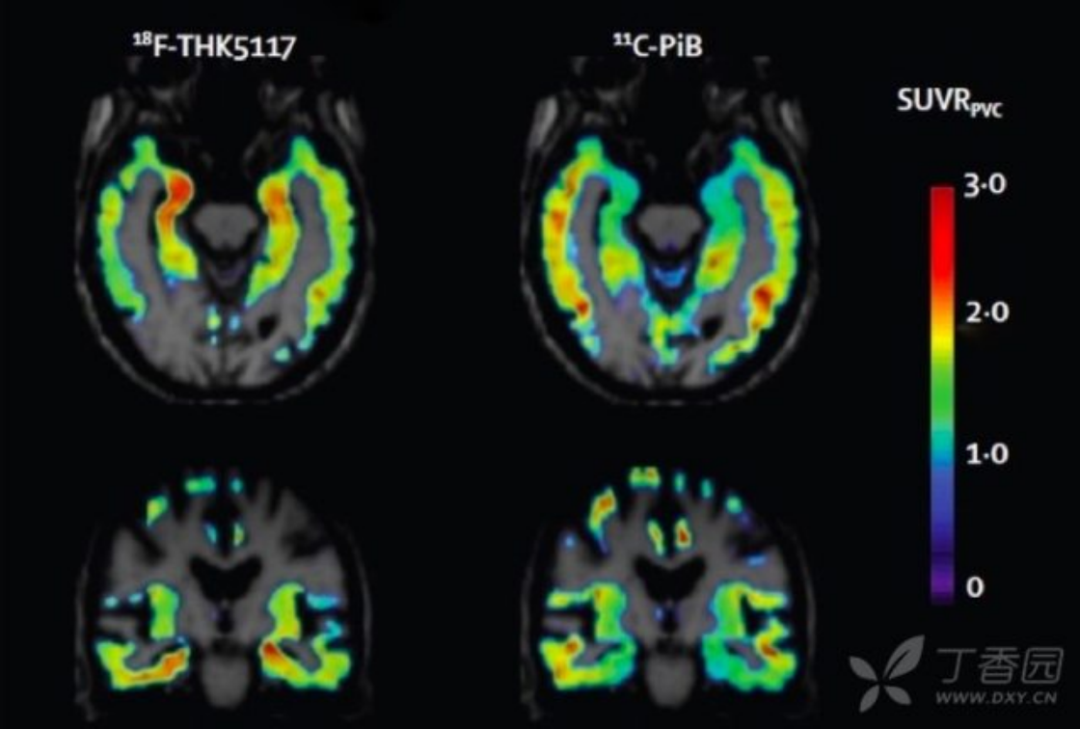

7. tau 蛋白成像 利用 tau 蛋白的氟化配体进行 tau 蛋白成像目前也是研究热点。Tau 蛋白配体聚集与 AD 临床症状符合;且与 Amyloid PET 相比,与基础代谢率减退和脑萎缩更相关。目前 Tau 成像主要用于临床药物试验,对于其临床诊断价值仍需进一步证实。

图 8 AD 患者以 18F-THK5117 和 11C-PiB 为显影剂的 tau 蛋白和 Aβ成像